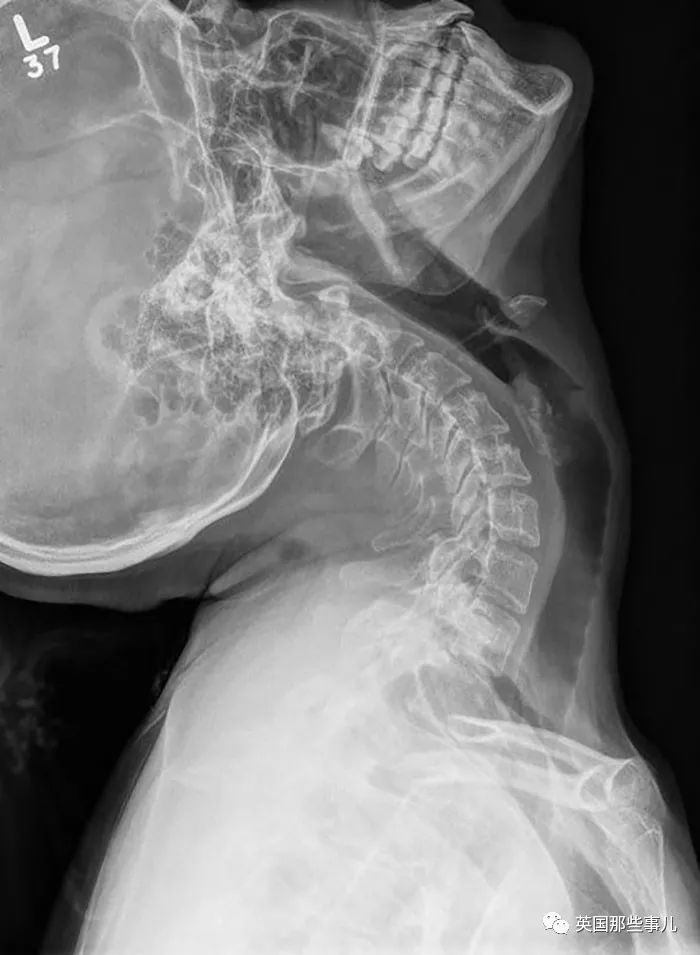

醫生在我爸爸的脖子裏植入了一個(ge) 裝置,裏麵含有未發育的骨細胞和幹細胞,用來幫助他的部分脊椎再生,科學真是太偉(wei) 大了。

我的頸椎太靈活了,把醫生都嚇了一跳....